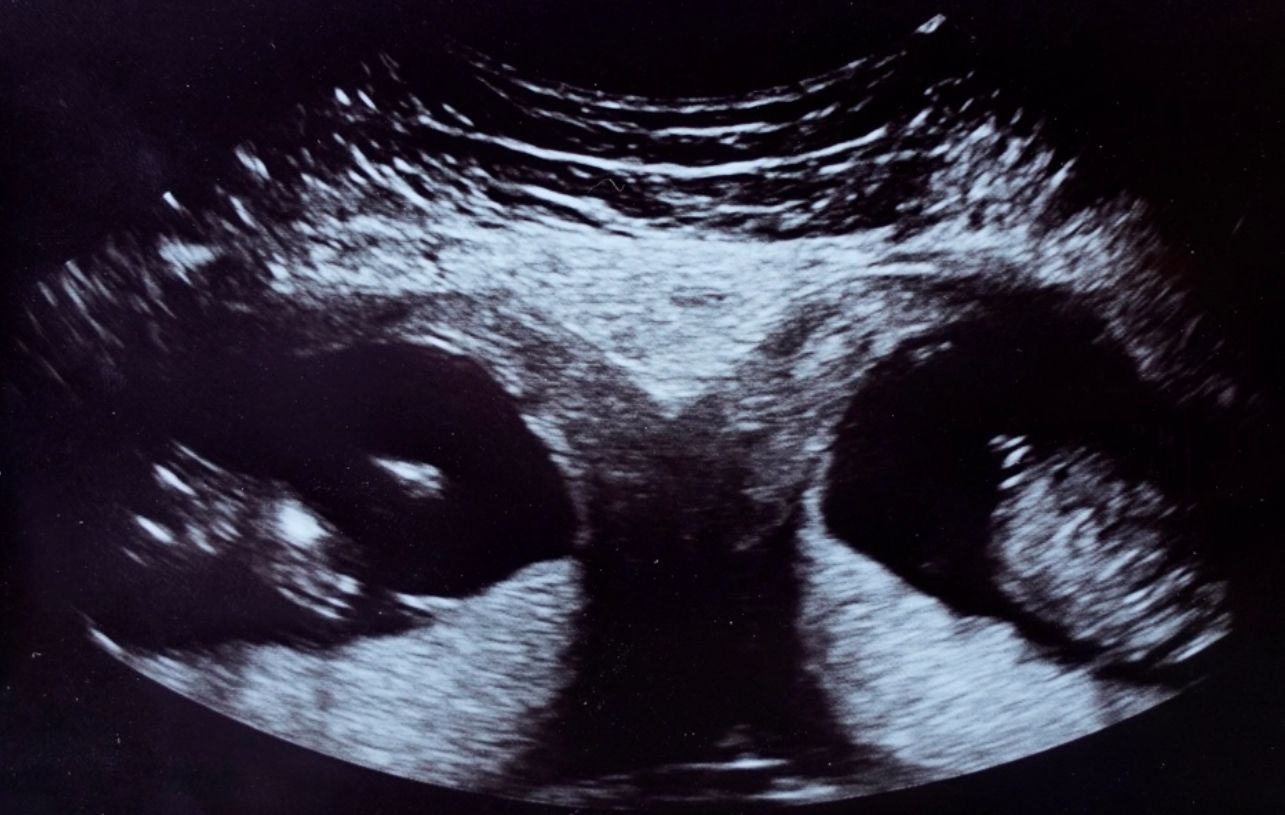

Zdjęcie USG, które pokazało nietypowe zmiany w organizmie Kelly (Facebook)

Kelly Fairhurst nie miała świadomości, że ma dwie macice. Dowiedziała się, kiedy zaszła w ciążę. Lekarze poinformowali ją, że urodzi bliźniaki. Dzieci rozwijają się jednak w dwóch różnych organach.

Sprawa jest o tyle zaskakująca, że kobieta ma już dwie córki. Do tej pory jednak nie zauważono, że coś może być nie tak. Bliźniaki, które rozwijają się w dwóch łonach matki, mogą być identyczne. Lekarze obawiają się, że bliźniaki mogą urodzić się przed terminem. Ze względu na to, że dzieci istnieje ryzyko, że będą konieczne dwa oddzielne porody.